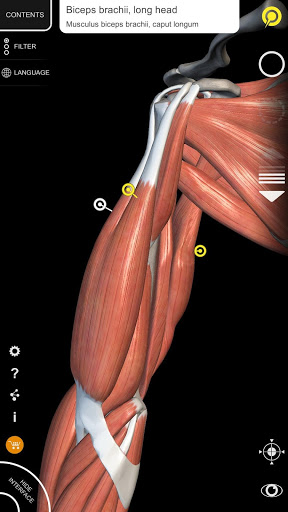

• تصور العضلات من خلال مستويات الطبقات من الطبقات السطحية إلى الأعمق

• من خلال تحديد نموذج أو دبوس، يظهر المصطلح التشريحي ذي الصلة

• وصف العضلات: الأصل والإدخال والتعصيب والعمل